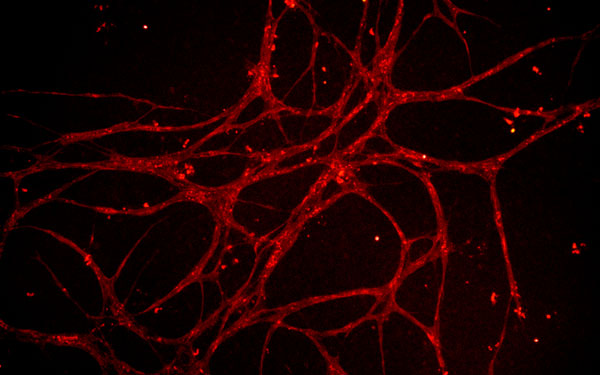

blood vessels grown in culture from rat adipose